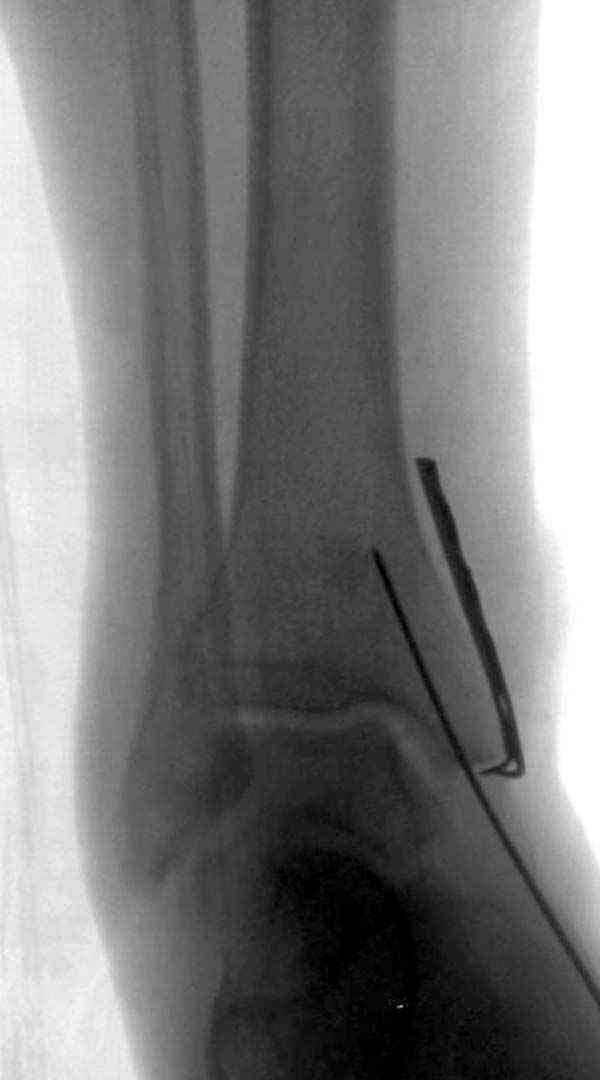

Нет первичных снимков, перелом очень низкий и под большим сомнением диагноз разрыва синдесмоза. Медиальная сторона отрепонирована на "хорошо" и, по-видимому, прорезание проволоки произошло во время операции. Без снимков трудно судить о высоте малоберцовой, а лодыжка находится в варусе. Лагирование получилось, но возле тонких шурупов передне-задний шуруп выглядит немного тяжеловато.

Во всех руководствах АО имеется описание техники применения низкопрофильных пластин 1/3 трубки, которые могут быть применены для фиксации наружной лодыжки. Фиксацию проводят кортикальными 3.5 мм шурупами, и если дистальная фиксация недостаточная, тогда усиливают конструкцию созданием hook plate. Сгибая конец пластины на последнем отверстии, внедряют его в дистальный отдел, и тем самым создается дополнительная фиксация.

Здесь несколько частных случаев: перелом голеностопа со сравнительными снимками и разрыв синдесмоза, а также медиальная Hook пластина.